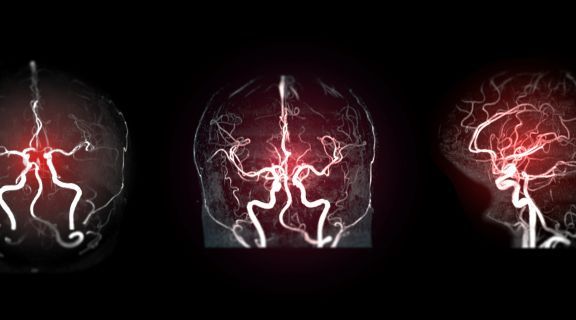

Em muitos casos, identificar um aneurisma antes do rompimento pode permitir um acompanhamento mais seguro e a definição do melhor momento para intervir. Para pessoas com fatores de risco, exames de imagem ajudam a mapear os vasos cerebrais e avaliar possíveis alterações.

Com o avanço da tecnologia, tratamentos minimamente invasivos podem ser indicados, permitindo acessar o aneurisma por dentro dos vasos e reduzir riscos. Essas abordagens tendem a oferecer mais precisão, menor impacto ao organismo e uma recuperação mais rápida.